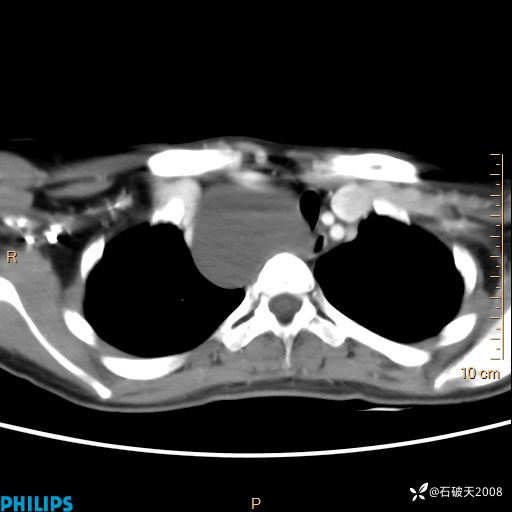

影像诊断要密切结合临床,真的很有必要(病理已公布)

女 21岁 主 诉:发现右侧颈部肿物18年余。

现病史:18年余前患者无明显诱因发现颈部偏右侧有一肿物,具体大小不明确,咳嗽、憋气时肿物增大,局部无疼痛,无吞咽不适,无胸闷及呼吸困难,至当地医院检查考虑良性病变(具体不详)并未做特殊处理,现患者自觉肿物随年龄增长而进一步变大,今日至我院行颈部CT平扫+增强提示:1.右侧颈根部、锁骨上窝及纵隔内异常密度影,考虑良性病变,淋巴管瘤?囊肿?请结合临床。2.双侧颈部小淋巴结。建议结合临床及其他相关检查。现为行进一步治疗,门诊以“颈部局部肿物”为诊断收住我科,发病来患者神志清,精神可,饮食睡眠可,大小便正常,体重无下降。

动脉期